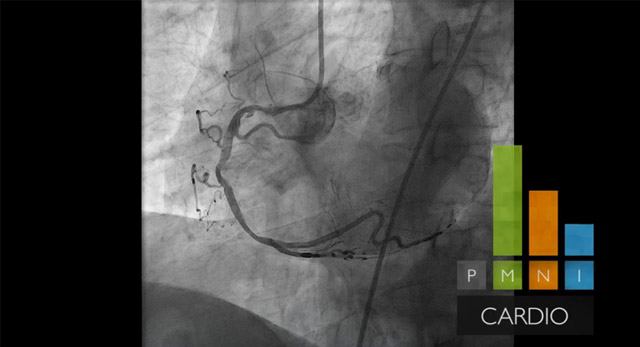

توفر أنظمة الأشعة السينية AlluraClarity المزودة بتكنولوجيا ClarityIQ تصويرًا عالي الجودة أثناء علاج أمراض الصمامات والعيوب الحاجزية وحالات الانسداد/الإطباق، بهدف منح الأطباء رؤية ممتازة بجرعات إشعاع منخفضة.

بعدا جديدا في مجال التصوير التدخلي يجمع الأشعة السينية والموجات فوق الصوتية

رؤية المقاطع التشريحية للأنسجة الرخوة ومسابر القسطرة/الأجسام المزروعة

يجمع جهاز EchoNavigator بين التوجيه بالأشعة السينية المباشرة وتخطيط الصدى ثلاثي الأبعاد في إجراءات إصلاح أمراض القلب الهيكلية (SHD)، مما يمنح مزيدًا من الثقة عند التشريح واستهداف الأجهزة، ويحسّن فعالية الإجراءات التداخلية.